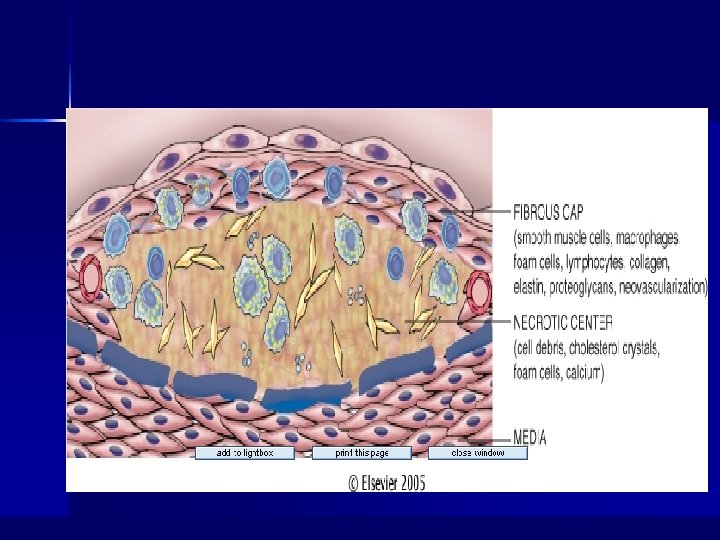

Summary of Atherosclerotic Process n n n n n Multifactorial process (risk factors) Initiated by endothelial dysfunction Up regulation of endothelial and leukocyte adhesion molecules Macrophage diapedesis LDL transcytosis LDL oxidation Foam cells Recruitment and proliferation of smooth muscle cells (synthesis of connective tissue proteins) Formation and organization of arterial thrombi

Fibrous Plaques Complicated Lesions

Complicated Lesions